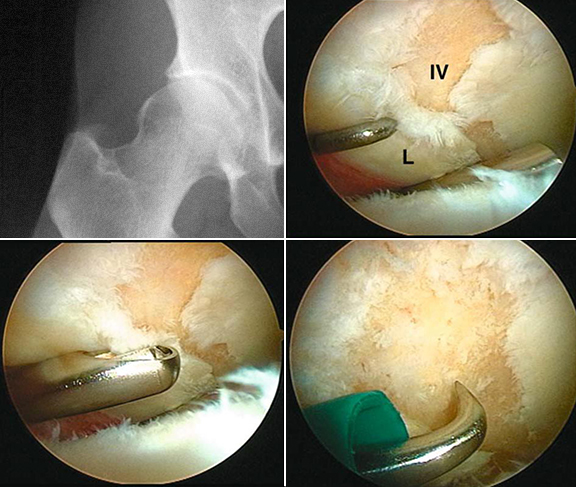

6 – Sinovite vilonodular – exérese de vilosidades.